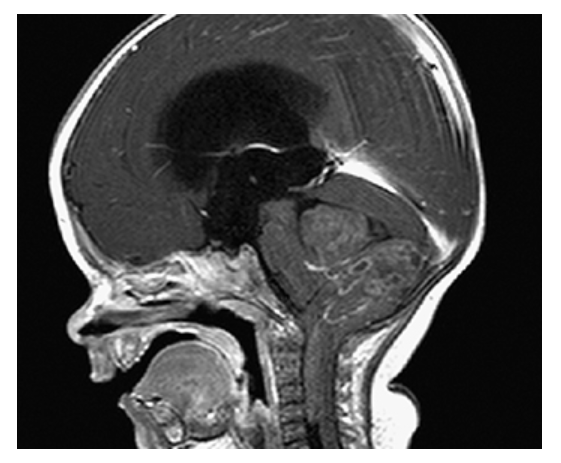

Dandy-Walker Syndrome. Sagittal T1W image shows a massively dilated fourth ventricle, expanded posterior fossa, high-riding torcula, and hypoplastic cerebellum.